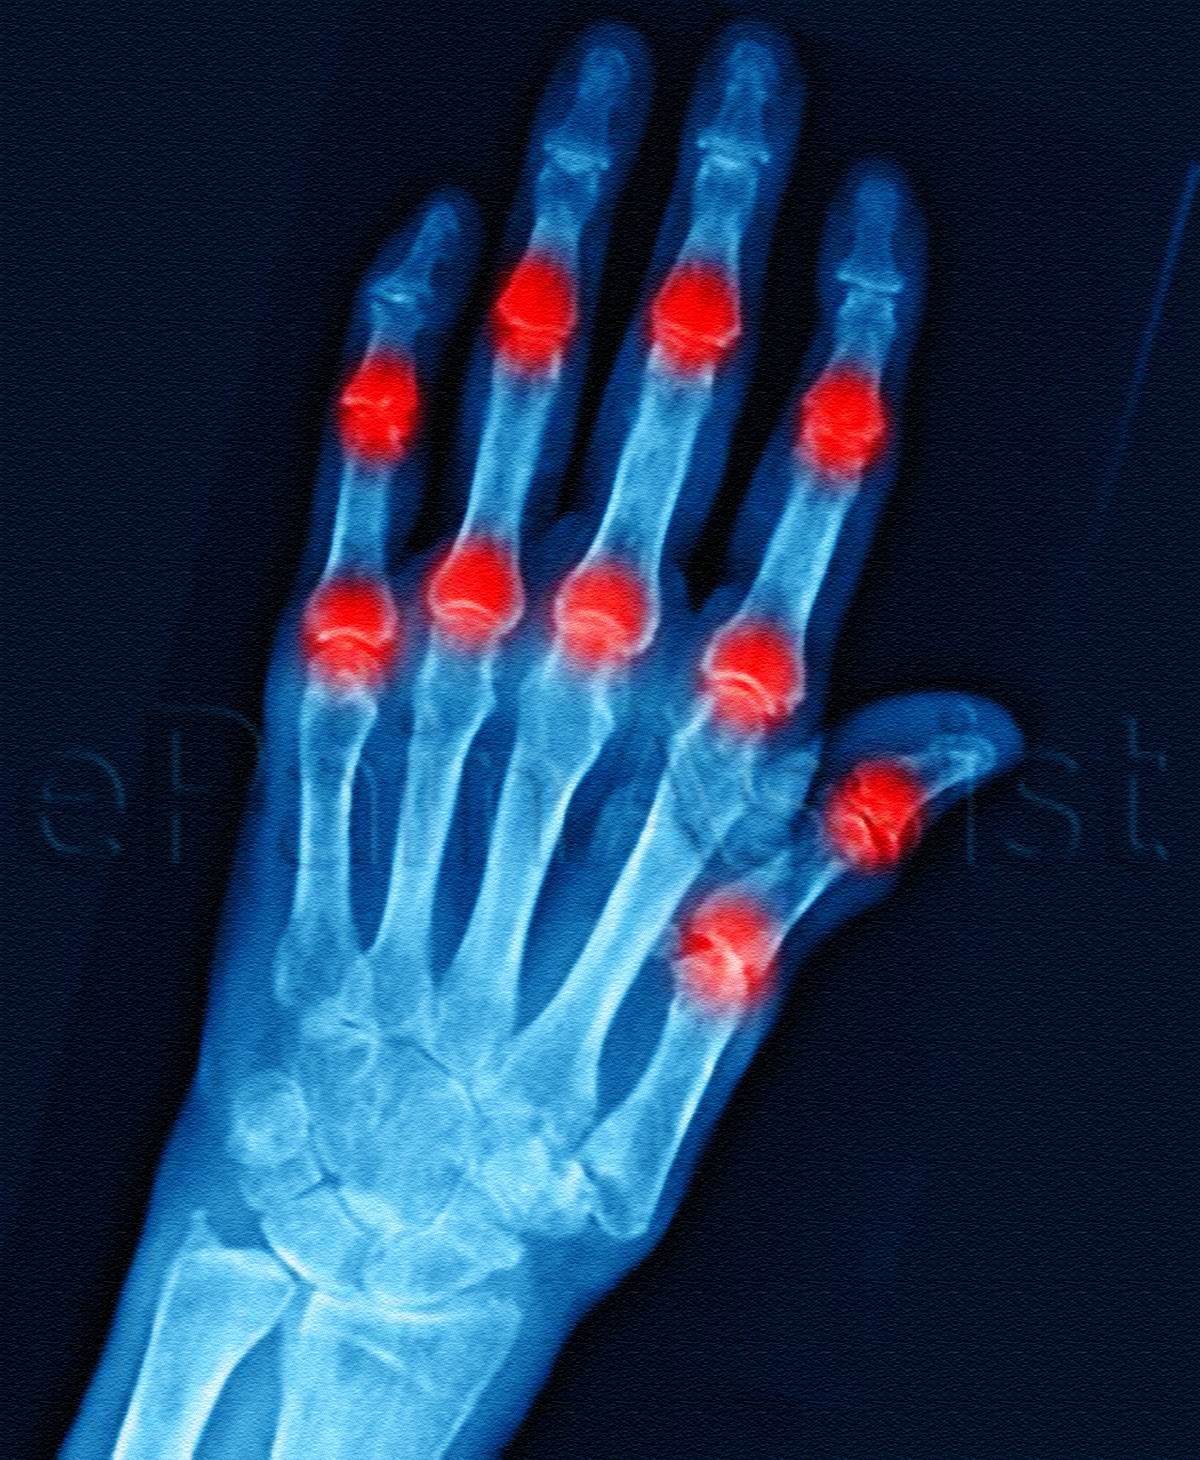

What is Arthritis (Joint Inflammation)?

Arthritis is a medical condition where there is inflammation of the joints. Symptoms chiefly comprise of stiffness and pain in the joints. These symptoms increase in intensity as the patient ages. Osteoarthritis and rheumatoid arthritis are the two commonest types of arthritis. The cause of osteoarthritis is wear and tear of the joints. Rheumatoid arthritis, on the other hand, is an autoimmune disorder. Whereas, the rest of the types of arthritis may be caused by infection, uric acid crystals, or other underlying medical disorders (psoriasis, lupus). Treatment depends on the type of arthritis and the main aim of treatment is to alleviate or decrease the intensity of the symptoms so that the patient can lead a better quality of life.

- Pain and tenderness in the affected joints.

- Stiffness in the affected joints.

- Swelling in the affected joints.

- Redness in the affected joints.

- X-rays help in assessing the cartilage loss, damage to the bone, and bone spurs. They also help in tracking the progression of arthritis.